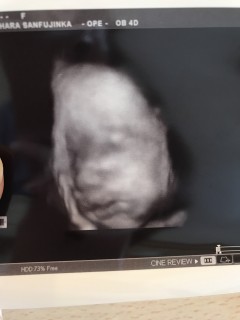

今日、検診に行って来ました! 体重は1992gだそうです! いつも4Dで顔を見る事が出来ず残念だったのですが、横顔が見れて嬉しかったです(^_^)目は線で書かれてしたいました!笑